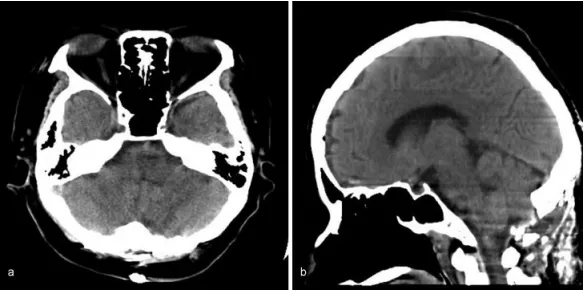

术中神经生理监测(运动诱发电位和感觉诱发电位)保持稳定。术中未发现海绵状畸形等病理学证据。术后CT显示血肿消失。

术后计算机断层扫描显示延髓血肿消失。